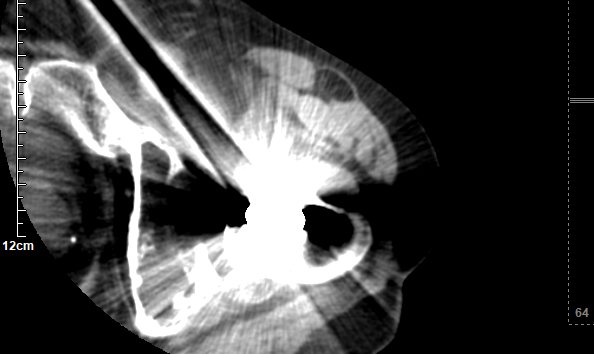

对比图像清晰显示:3月11日常规平扫图像中,金属伪影严重,结构显示不清;而3月12日采用MAR技术扫描后,无论是横断面还是冠状位重建图像,金属伪影均基本消除,解剖结构清晰可见,为临床精准评估和假体设计提供了可靠依据。

注:以下图片展示了常规平扫与MAR技术扫描的对比效果,清晰呈现金属伪影消除技术的临床价值。

普通平扫(金属伪影较重)